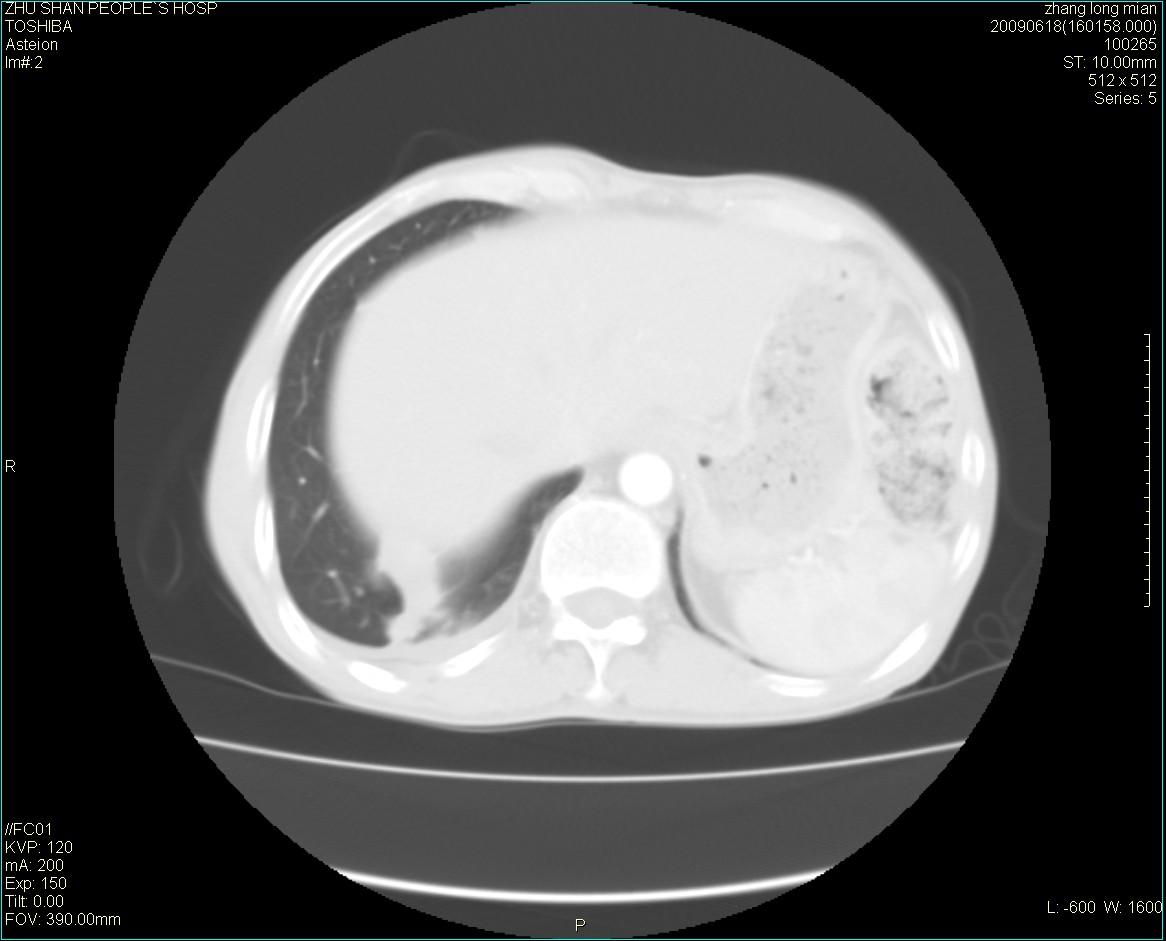

男性 65岁 胸片发现右下肺包块.诊断肺ca并纵隔转移没有问题吧!

两侧胸廓不对称,右侧呈塌陷改变,右肺萎缩。

右下肺见浅分叶状软组织块影,边缘有毛刺,其下部似见不完整偏心空洞影,邻近胸膜凹陷征,并胸腔积液。

增强见纵隔区气管隆突上下及左肺门区肿大淋巴结。左肺感染性病灶。

另见右上肺见一枚小结节影,性质待定。